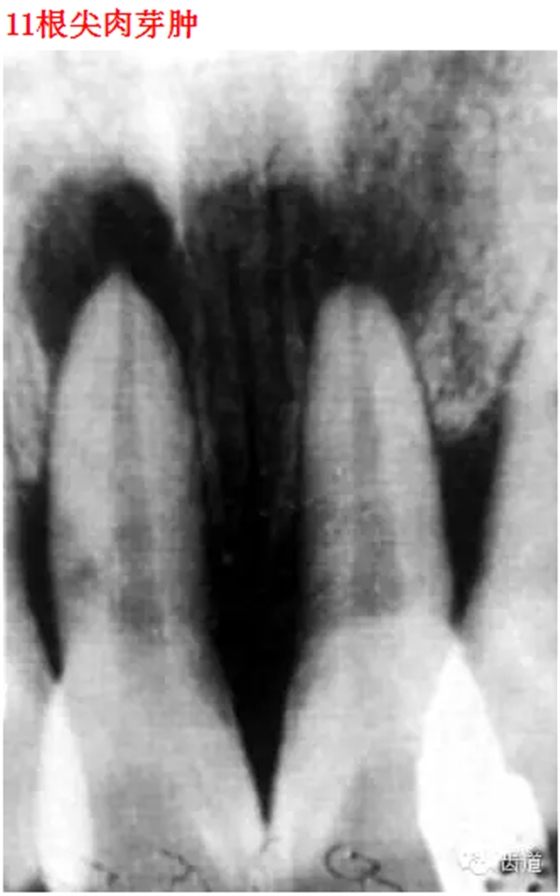

26種口腔病變X光片